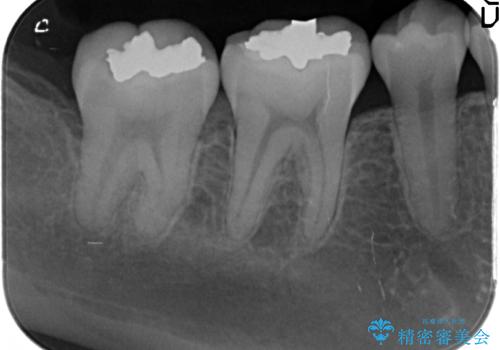

- 笑った時に見える銀歯を外したいと希望され来院されました。

銀歯の下には初期の虫歯も見られたので、除去後精密なシリコン印象を行いセラミックインレーを製作しました。